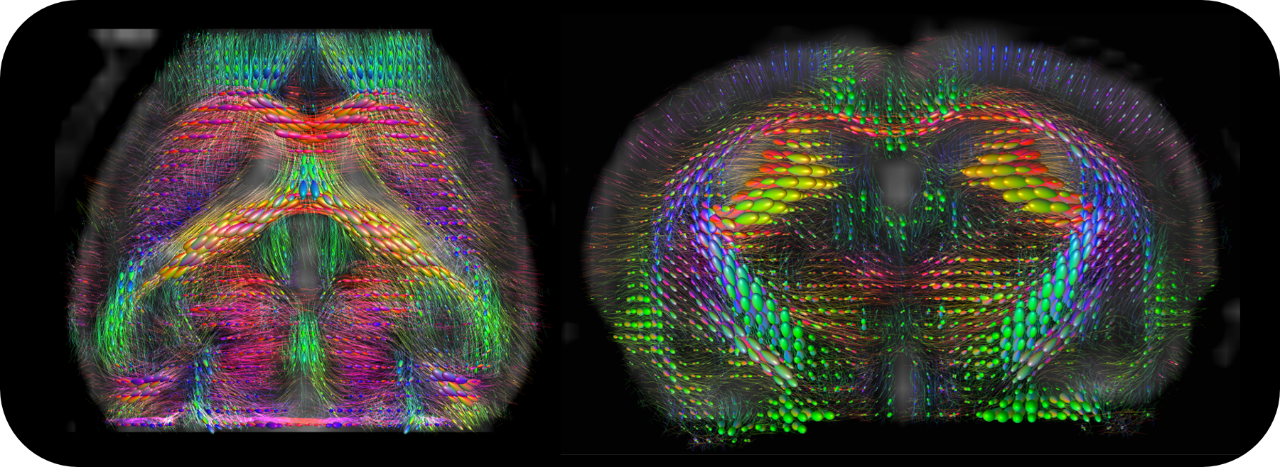

• High performance BGA-S-HP gradients with highest amplitudes and slew rates, shim strengths and duty cycles

• Fast and easily mountable gradient/shim inserts for optimum gradient/shim performance for small samples available

• Complete RF coil portfolio for mice and rats available, including coils for head, brain, cardiac, body, optogenetics, Arterial Spin Labeling, multi-channel array coils with up to 16 channels, and x-nuclei

• MRI CryoProbes with 2 element, 4 element, or as 13C for mice as well as 4 element for rat delivering an exceptional increase in sensitivity